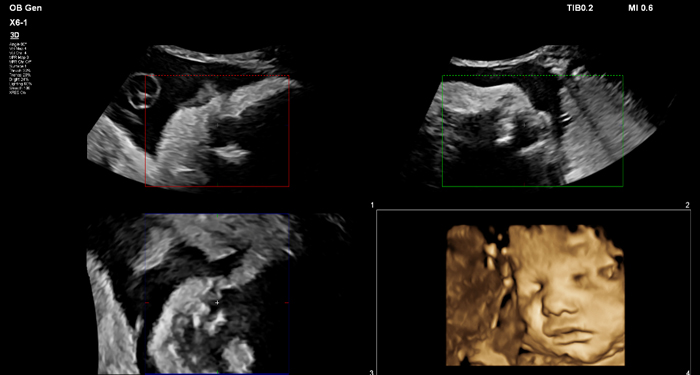

At the touch of a button, the new MaxVue high-definition display brings extraordinary visualisation of anatomy with 1,179,648 additional image pixels compared to a standard 4:3 display format mode. MaxVue enhances ultrasound viewing during interventional procedures and provides 38% more viewing area to optimise the display of dual, side/side, biplane, and scrolling imaging modes.

MaxVue offers a 38% greater viewing area.